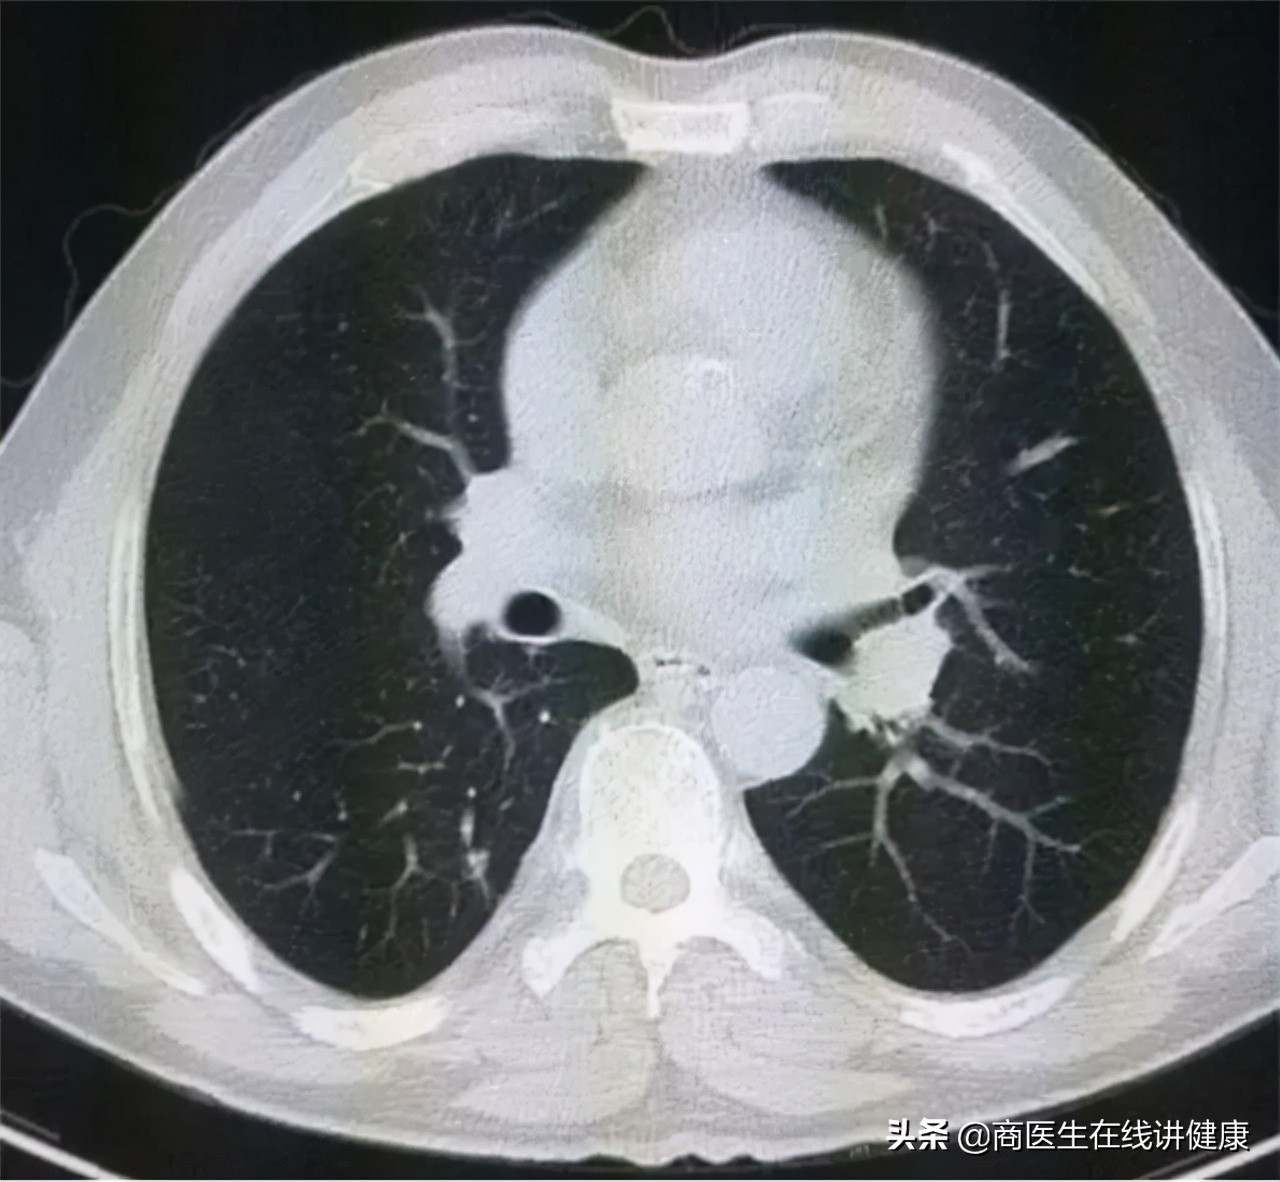

经过对患者叶女士询问后,我们首先推荐患者去做胸部CT。拿到CT结果后,发现患者果然在双肺多处均有结节状影像,存在多发性结节的情况。从CT上看,结节的大小和实性均不一。但从大小上看,都属于微小结节,且性质上也均属于毛玻璃状。

连续入院治疗十天后,患者叶女士咳嗽及咳痰等症状已明显缓解,随后再次做了肺部CT复查,CT检查结果显示,多个肺部结节已经通过治疗后消失,仅有右肺下叶处一个结节仍在影像结果中有显示,但对比入院的CT结果来看,此结节的影像也有所变淡,但大小并无明显变化。

就治疗结果来看,除了此处这一结节暂时不能确定其性质,其他多处结节已证实,均为炎症所致,入院治疗的效果非常好。